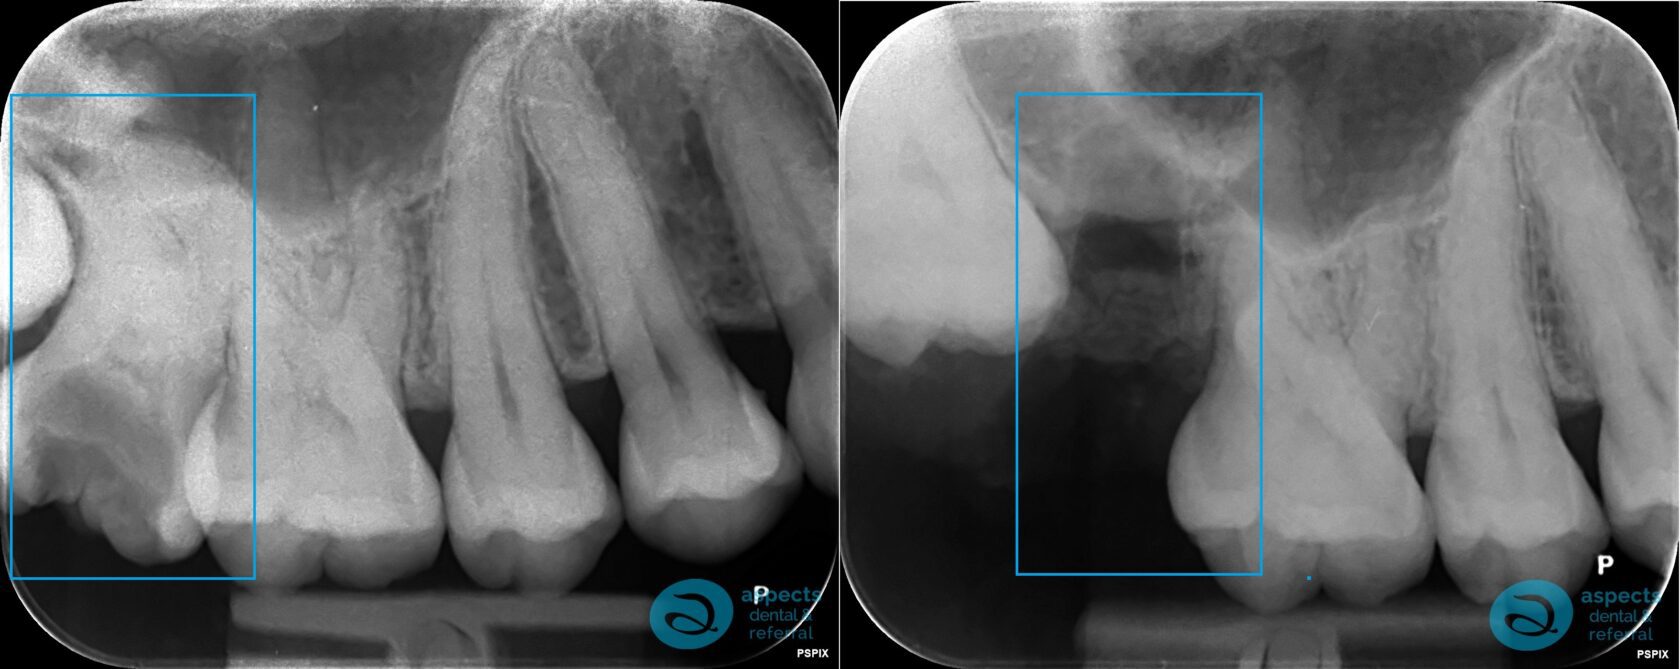

The affected tooth was grossly carious, featuring severely curved roots and lying in close proximity to the adjacent third molar (wisdom tooth). Due to the complexity of the root anatomy and positioning, a surgical extraction was indicated rather than a routine removal.

In this particular case, our Milton Keynes Dentist performed a minimally traumatic surgical technique, carefully removing all root apices intact while preserving the surrounding bone and soft tissues.